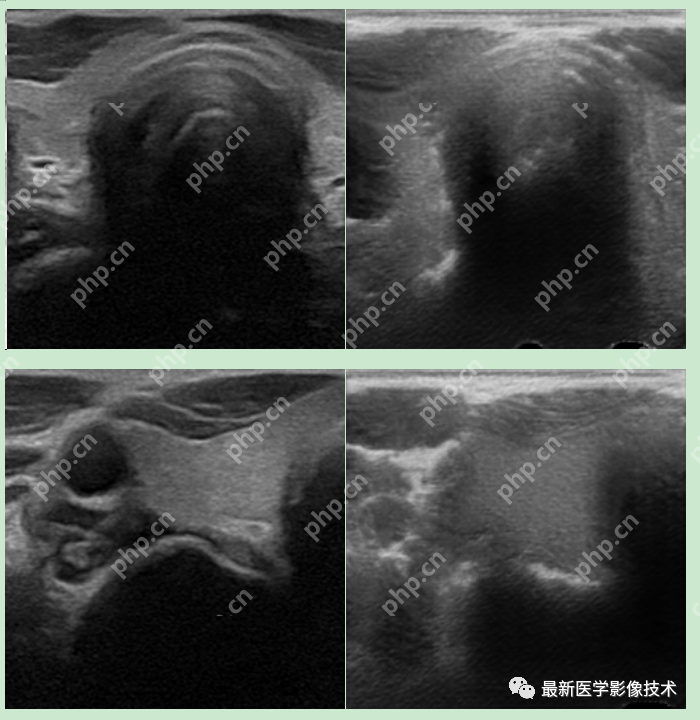

6、测试集部分生成结果

左图为低质量图像,右图为生成的高质量图像。